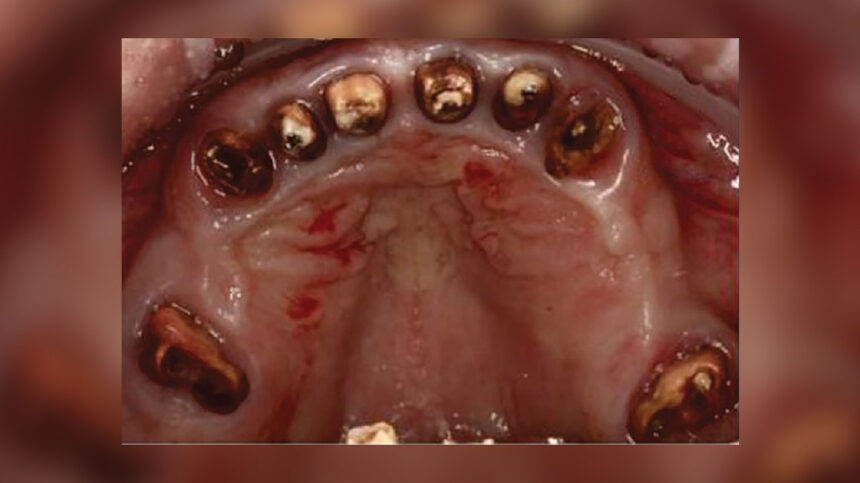

Εισαγωγή Ανάμεσα στα πιο συνήθη προβλήματα στην σύγχρονη οδοντιατρική είναι αυτό της αποκατάστασης της οδοντικής [...]

Το άρθρο αυτό του Dr Randolph Todd περιγράφεται η αντιμετώπιση μίας πρόκλησης του παρελθόντος, συγκεκριμένα [...]